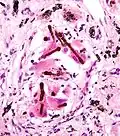

Согласно гистологической классификации рак лёгкого подразделяется на следующие виды:

I. Плоскоклеточный (эпидермоидный) рак

_by_core_needle_biopsy.jpg)

II. Мелкоклеточный рак

III. Аденокарцинома

IV. Крупноклеточный рак

V. Смешанный рак

Гистологическая характеристика рака лёгкого достаточно условна, поскольку клиническое течение может сильно различаться даже для опухолей с одинаковой структурой. Медленнее всего растёт дифференцированный плоскоклеточный рак; для недифференцированного рака характерно быстрое течение с обширным метастазированием. Мелкоклеточный рак лёгкого принадлежит к числу самых злокачественных опухолей. Он отличается коротким анамнезом, скрытым и быстрым протеканием, ранним метастазированием, плохим прогнозом.